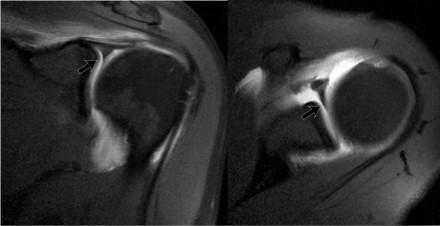

Варианты строения суставной губы

Существует много вариантов строения суставной губы.

Эти вариатны нормы локализуются в области 11-3 часов.

Важно уметь распознавать эти варианты поскольку они могут симулировать SLAP-повреждения.

За повреждение Банкарта, эти варианты нормы обычно не принимают, поскольку оно локализуется в позиции 3-6 часов, где анатомические варианты не встречаются.

Подгубное отверстие

Подгубное отверстие - отсутствие прикрепления передневерхних отделов суставной губы в области 1-3 часов.

Определяется у 11% населения.

При МР-артрографии подгубное отверстие не должно приниматься за подгубное углубление или SLAP-поврежедение, которые также локализуются в данной области.

Подгубное углубление расположено в области прикрепления сухожилия двуглавой мышцы плеча на 12 часов и не распространяется на область 1-3 часов.

SLAP-повреждение может распространятся на область 1-3 часов, но всегда должно быть вовлечено прикрепление сухожилия двуглавой мышцы.

Пролистывайте изображения и обратите внимание суставная губа не прикреплена в области 12-3 часа, в области подгубного отверстия.

Обратите внимание гладкие края, в отличии от SLAP-повреждения.

Комплекс Буфорда

Комплекс Буфорда это врожденный вариант строения суставной губы в виде отсутствия ее передневерхних отделов в области на 1-3 часа и утолщение средней плече-лопаточной связки.

Определяется в 1,5 % случаев.

На аксиальных изображениях слева может быть виден комплекс Буфорда.

Отсутствуют переднеие отделы суставной губы в области на 1-3 часв, утолщена средняя плече-лопаточная связка.

Утолщенная средняя плече-лопаточная связка не должна обшибочно приниматься за смещенную суставную губу.

Всегда по возможности необходимо прослеживать ход средней плече-лопаточная связки сверху вниз от фиброзно-хрящевой губы гленоида к плечевой кости.